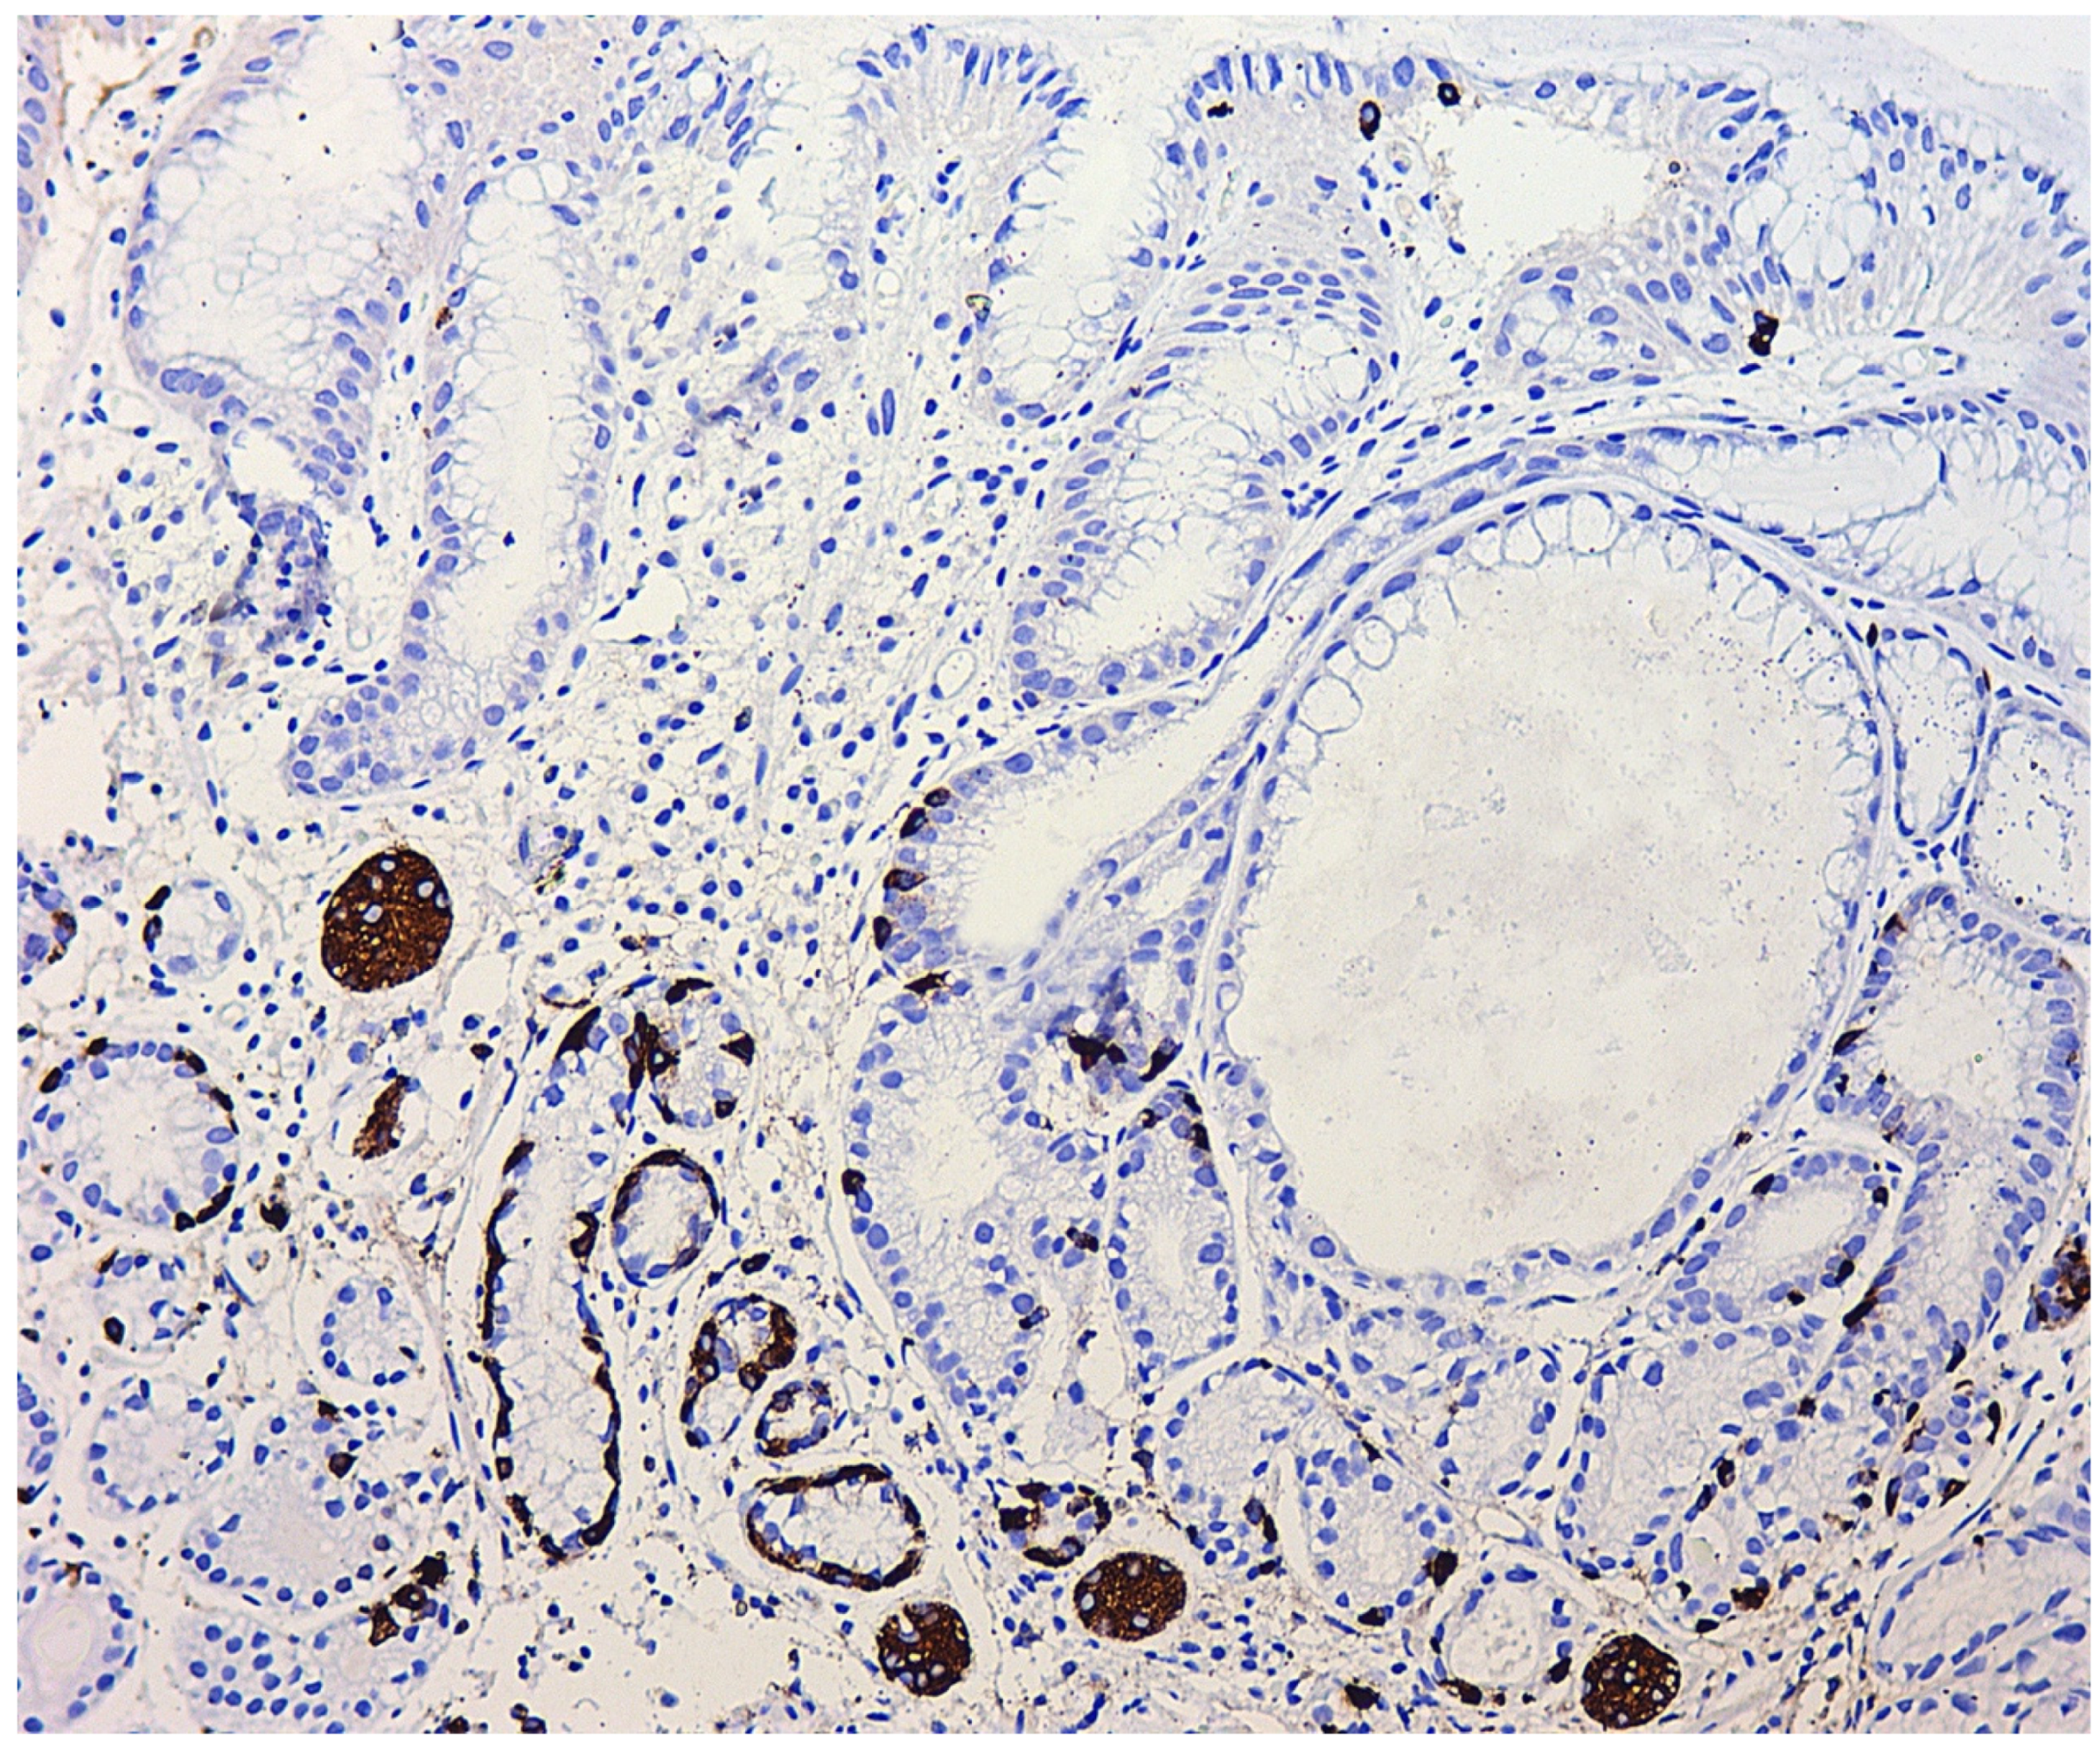

- Linear hyperplasia. The presence in one visual field of at least two groups of linearly located neuroendocrine cells, consisting of five or more cells. Usually, changes are diagnosed in the area of the neck glands (Figure 4).

- Adenomatous (adenomatoid) hyperplasia. The presence of an aggregate of five or more clusters (Figure 5).